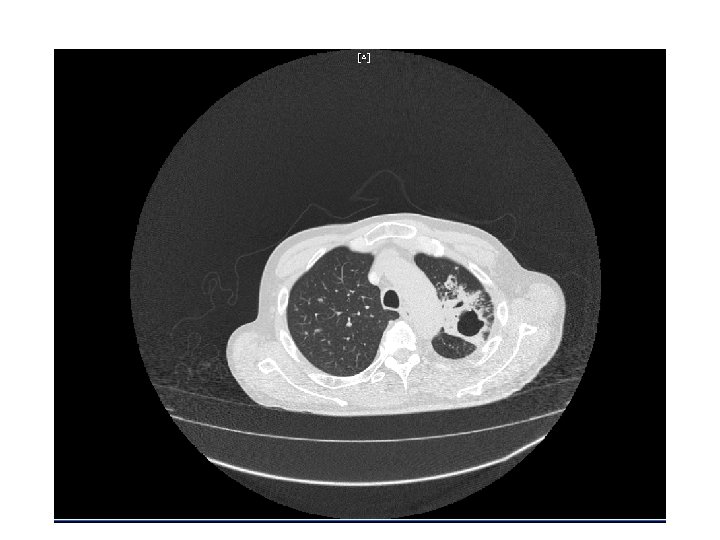

CT Chest • Multiple cavitary lesions • Largest left lung apex 3. 8 x 4. 7 cm with nodular thickened wall • Smaller cavitary lesions in L lung base • R lung: smaller areas of ground-glass opacities with areas of tree in bud appearance.